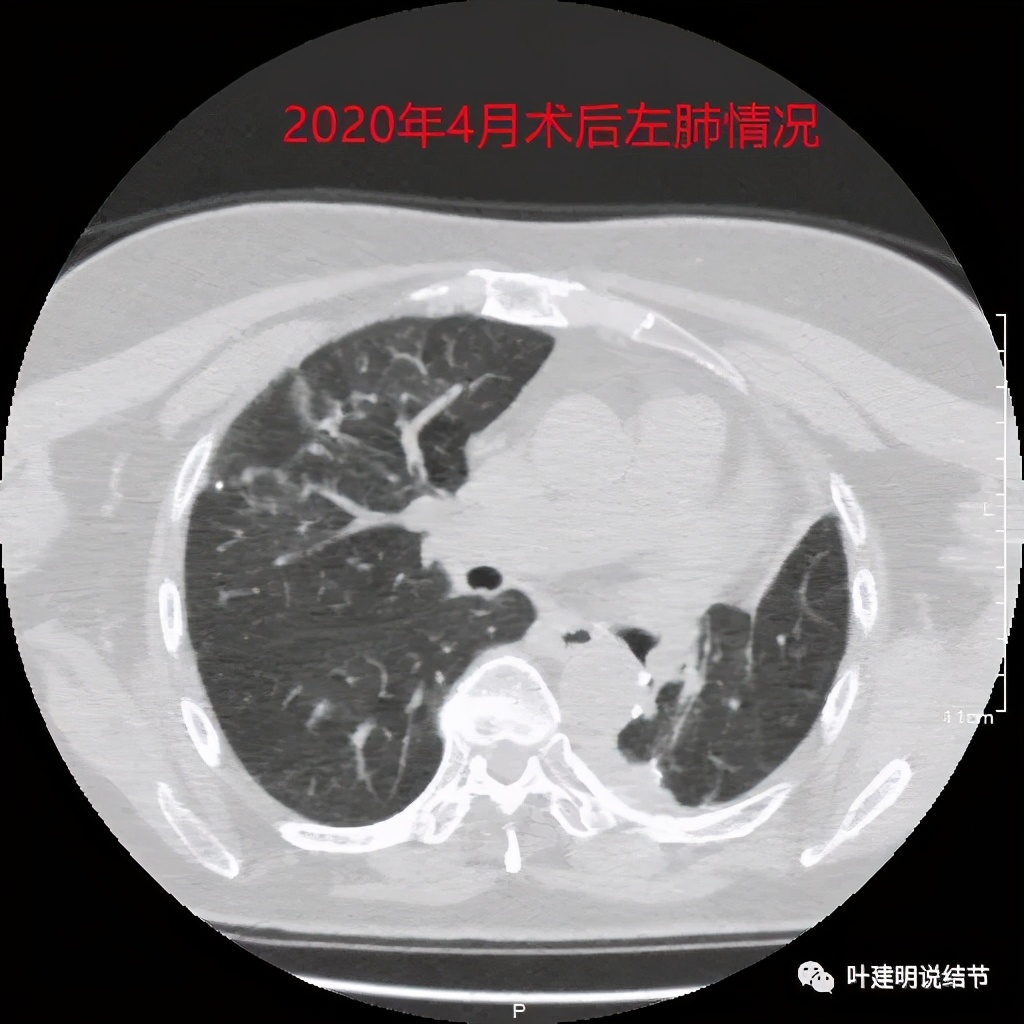

到了当年8月,残肺张的好了点

到了术后一年左右,左残肺膨的大多了,关键时积液明显吸收好转,纵隔也移过来,肺功能逐渐有所改善。